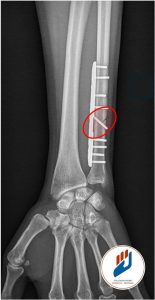

Des examens d’imagerie sont ensuite prescrits pour confirmer le diagnostic. Les radiographies standards du poignet permettent de mesurer la longueur relative du radius et du cubitus (variance ulnaire). Une IRM ou un arthroscanner permet de visualiser les lésions du fibrocartilage triangulaire et l’état des surfaces articulaires (le cercle rouge sur la photo montre une usure du cartilage sur le pôle proximal du semi-lunaire).

Lorsque le cubitus est clairement trop long ou si le poignet présente des lésions cartillagineuse entre l’ulna et le semi-lunaire, une ostéotomie de l’ulna est indiquée. Cette opération consiste à retirer quelques millimètres d’os au niveau du cubitus (zone entouré par le cercle rouge sur la photo) et à fixer l’os avec une plaque et des vis. Ce geste corrige durablement le conflit mécanique et permet une amélioration significative des douleurs. L’immobilisation post-opératoire est de 6 à 12 semaines, et la rééducation se poursuit sur plusieurs semaines. La plupart des patients reprennent une activité professionnelle manuelle entre trois et six mois après l’intervention.